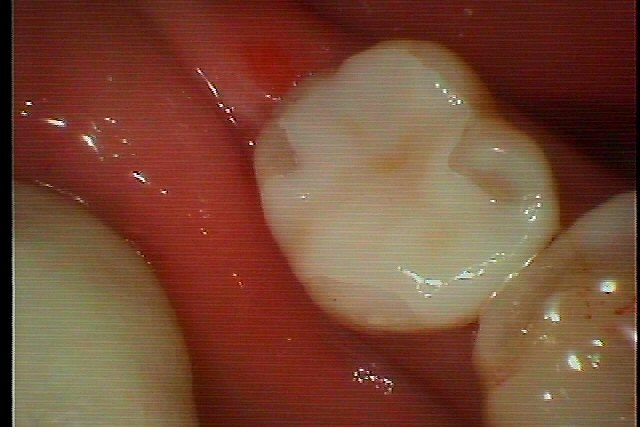

右下6番になります

この歯を白いセラミックを入れていきます

深い虫歯を除去していきました

白いきれいなセラミックにて修復していきました